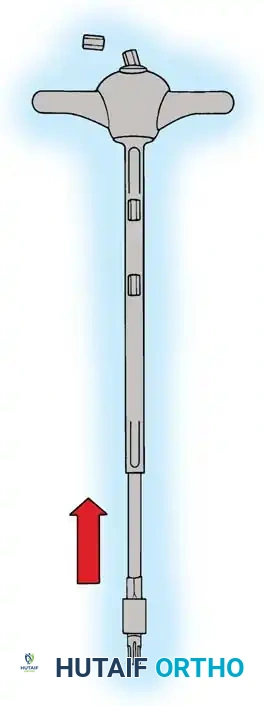

Posterior Surgeries for Idiopathic Scoliosis: A Masterclass in Surgical Technique

The posterior approach remains the workhorse for the surgical correction of adolescent idiopathic scoliosis. It provides extensile, safe access to the entire vertebral column, facilitating multi-segmental instrumentation and robust arthrodesis. Success relies on meticulous patient positioning to preserve sagittal alignment, precise subperiosteal exposure to minimize blood loss, and rigorous facetectomy and decortication to ensure a solid, long-lasting spinal fusion.

The posterior approach to the spinal column remains the most universally utilized and versatile corridor for the surgical management of adolescent idiopathic scoliosis (AIS). Familiar to all fellowship-trained orthopaedic spine surgeons, this extensile approach offers safe, comprehensive exposure of the entire vertebral column. It facilitates the application of modern multi-segmental pedicle screw constructs, allows for aggressive posterior column osteotomies, and provides a massive surface area for robust arthrodesis.